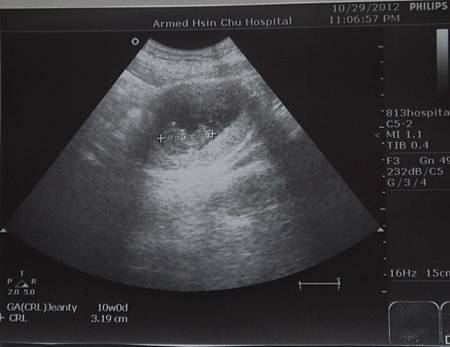

【10W】小ET形成

孕期邁入了第十週

照慣例的躺上小床會吾兒

小籠包量量身高

只有3.19公分

好小喔

雖然現在手和腳都還小小的

可是這看起來好像在翹腳喔

不過這主要是醫生要看頸部透明帶啦

やっと会えた。3.19CMだった。

鼻が見えた、変なポーズをとってた。